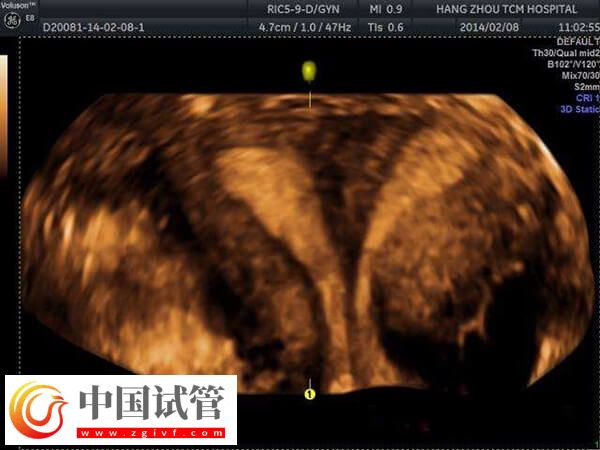

移植優(yōu)胚出現(xiàn)的空囊的患者,可能是存在宮腔環(huán)境異常,如宮腔粘連、縱膈子宮等,會影響胚胎發(fā)育,導致妊娠空囊。這些情況通常需要通過宮腔鏡下手術分離粘連或縱膈來改善。